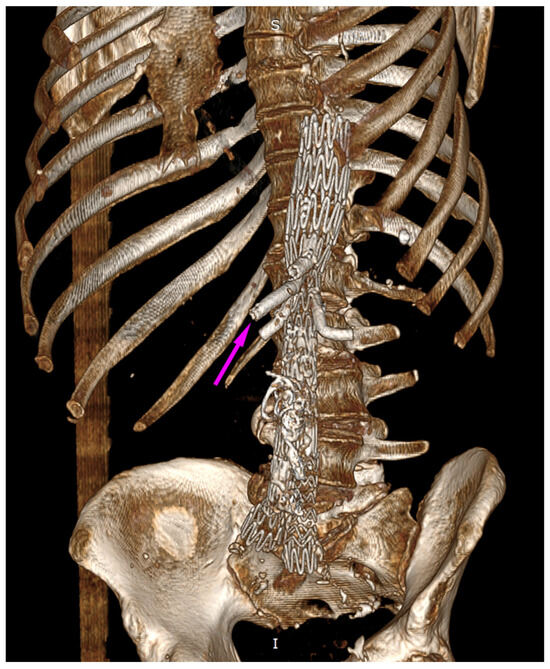

We present the case of an 82-year-old male patient who appeared in the emergency department due to progressive weakness and abdominal pain (2024). Due to a drop in blood pressure to 80/40 mmHg, a continuous infusion of norepinephrine was initiated. The hemoglobin level was approximately 5.1 g/dL. His medical history included generalized atherosclerosis, renal failure, and a thoracoabdominal aortic aneurysm (TAAA) treated with endovascular aneurysm repair (EVAR) using stent-graft implantation 4 years earlier (2020). At that time, the angio-CT scan revealed an aneurysm starting just below the celiac trunk, extending to the superior mesenteric artery (SMA) and both renal arteries (RAs). The maximum diameter of the aortic aneurysm was 51 mm; however, the left common iliac artery measured 41 mm in diameter, an indication for thoracoabdominal stent graft implantation. The aortic aneurysm itself was completely free of mural thrombus. The patient had also experienced a heart attack 16 years earlier and a transient ischemic attack (TIA) 2 years earlier. Following the stent graft implantation, he underwent multiple successful interventions to address endoleaks. One year after implantation, endovascular treatment with embolization coils was performed to eliminate leakage from the lumbar artery (LA) (2021). Three years post-implantation, he was admitted to address leakage from the inferior mesenteric artery (IMA) using embolization coils as well (Figure 1) (2023). In 2024, an X-ray and CT scan revealed a rupture in a branch of the stent graft located in the SMA in its middle part, along with an enlarged aneurysm sac (74 mm) due to the fracture and leakage (Figure 2, Figure 3, Figure 4 and Figure 5). The angio-CT scan did not reveal any contrast extravasation beyond the vessel wall. However, significant contrast leakage was visible in the area of the visceral arteries within the aneurysm sac. The implanted device was the Zenith t-Branch Thoracoabdominal Endovascular Graft, and the ruptured branch was identified as the Bentley BeGraft (Bentley InnoMed GmbH, Hechingen, Germany). Urgent surgical intervention was performed. Intraoperative angiography (IA) showed a breach in the continuity of the BeGraft material within the SMA, with contrast leakage into the aneurysm sac (Figure 6 and Figure 7). To address the leakage and restore the continuity of the SMA branch, an additional BeGraft Plus 8 × 57 mm was implanted into the damaged branch. Subsequent IA and control CT scans confirmed the elimination of leakage, restoration of stent graft continuity, and revascularization of the SMA (Figure 8, Figure 9 and Figure 10). The surgery was completed without complications, and the patient was discharged home in good general condition. The patient returned for follow-up 3 weeks after the last intervention. An angio-CT examination was performed, revealing no enlargement of the aneurysm sac (74 mm), confirming the elimination of the endoleak, and demonstrating successful revascularization of the SMA. Ongoing follow-up will be continued.

Figure 1. Thoracoabdominal branched stent-graft in the lumen of aorta and visceral arteries. Embolization coils are marked with arrows. Abdominal X-ray.

Figure 6. Ruptured superior mesenteric artery branch of stent graft. The fractured site is marked with an arrow. Intraoperative X-ray.

Figure 7. Ruptured superior mesenteric artery branch of stent graft. Leakage outside the stent graft after administration of contrast to the SMA branch. Visible leakage into the aneurysm sac. The leakage is marked with arrows. Intraoperative angiography.